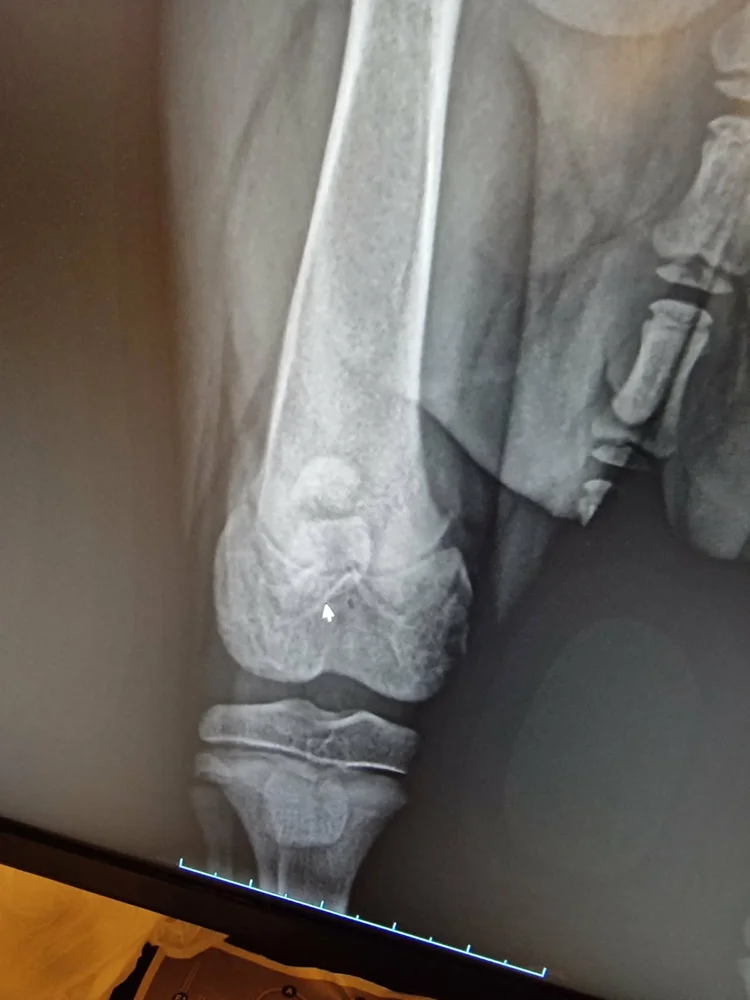

hei jeg har ei border collie tispe stella(13 uker) som har fått ledd skade i høyere bakfot og har nå behov for operasjon av ortoped og rehabilitering etter operasjonen for og kunne få et bra liv igjen å kan være en brukende gjeterhund når hun blir stor. Jeg har ikke penger til full rehabilitering og jeg setter stor pris på alle type bidrag som kan redde henne for at Stella hunden kan få et bra liv igjen. Det er veldig tøft for meg og vite at når valpen min nesten nettopp har startet livet sitt så må avlivning vurderes hvis jeg ikke har råd til rehabilitering for henne